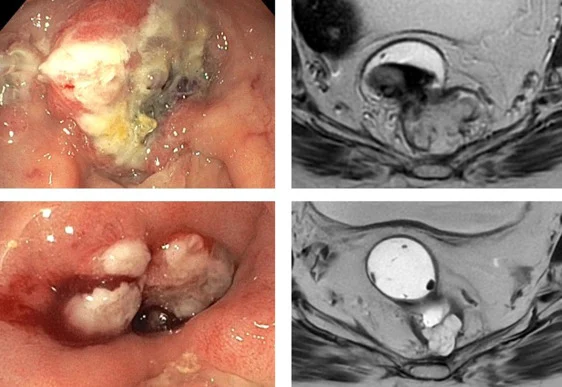

Title: Evaluating MRI response criteria in microsatellite instability-high rectal cancer treated with immune checkpoint inhibitors